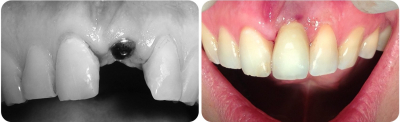

Gallery